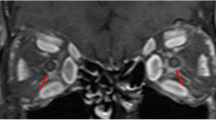

Patients diagnosed as thyroid-associated ophthalmopathy (TAO), with or without DON, and healthy participants were recruited. Vertical and horizontal sectional images of the optic nerve were collected by B-scan ultrasonography. ONSDs at 3 mm and 6 mm behind the eyeball were measured independently by two researchers. Multivariate regression analysis was performed to evaluate the association of ONSD with demographic and ocular parameters in TAO patients. Areas under the receiver operating characteristic curves (AUROCs) were applied to evaluate the diagnostic accuracy of ONSD for DON.

A total of 47 healthy eyes, 36 TAO eyes without DON, and 33 eyes with DON were studied. ONSDs at 3 mm and 6 mm of DON eyes were significantly higher than those in non-DON and healthy eyes (all P < 0.05). There was no significant difference in ONSDs between clinically active and inactive eyes (both P > 0.05). DON occurrence showed a positive association with both ONSDs at 3 mm (β = 0.49, 95% CI: 0.14–0.83, P = 0.007) and 6 mm (β = 0.58, 95% CI: 0.20–0.96, P = 0.003). ONSDs at 3 mm and 6 mm showed a desirable diagnostic capacity to distinguish DON from non-DON eyes (AUROC was 0.77 and 0.75, respectively).